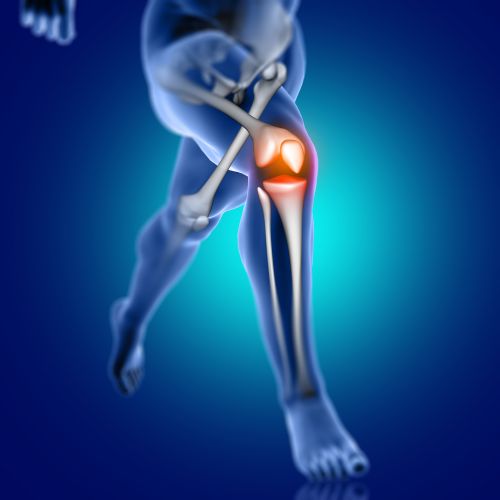

Comprehensive joint pain management including knee, hip, shoulder, and other joint conditions.

Sports

For people involved in active sports or recreational sports, injuries related to it are a common occurrence. They seem trivial and are often ignored initially, to recur later and cause that daily and constant ache in a body part affected by the sports injuries.

Most often, muscles, tendons and ligaments are affected in sports injuries. If not taken care of in time, they can lead to serious and career threatening injuries later in life.